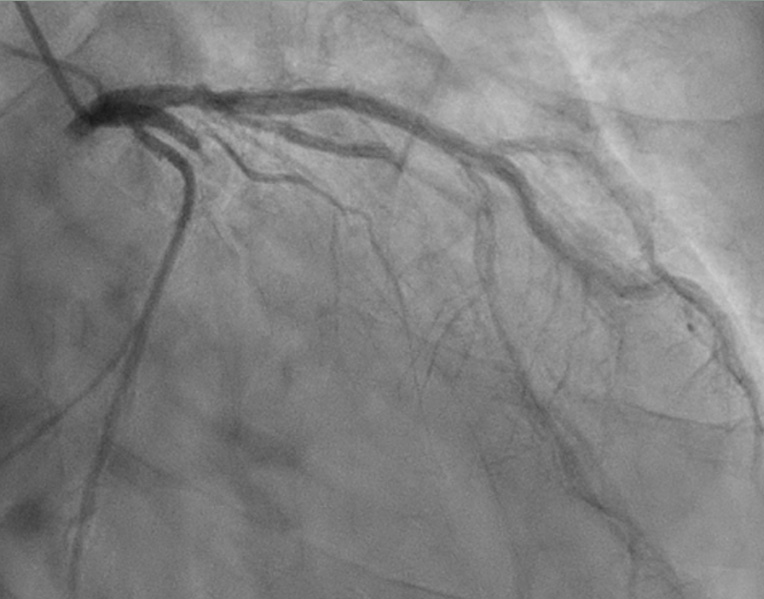

환자는 응급실로 내원해서 위와 같이 thrombotic occlusion이 있었던 분입니다.

Enzyme도 상승하였고,

PCI는 비교적 간단하게 풍선과 스텐트로만 하였습니다.

조영술 결과도 stenotic lesion도 아닌 폐색성 병변이고 혈관의 proximal occlusion으로 응급 시술이 필요했을 환자로 분류되어야 합니다. EF도 40% 전후입니다. 혈전성 폐색, 혈전 제거술을 포함한 스텐트 시술을 한 분으로 flow도 관련 근거에 부합한다고 판단합니다.